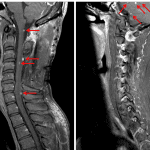

- Status post bilateral C3-C5 laminectomies

- Abnormal patchy T2/STIR hyperintensity in the cervical spinal cord, particularly dorsally, spanning C2-C3 through C7-T1 with associated mild cord expansion from C3-C4

- More discrete, smaller enhancing nodules eccentrically located within the cervical spinal cord from C3-C7 as well as at the cervicomedullary junction and in the incompletely imaged bilateral cerebellar hemispheres and vermis

- At C5-C6, a posterior disc-osteophyte complex indents the ventral cord and in combination with ligamentum flavum thickening results in moderate spinal canal stenosis without significant neural foraminal stenosis

- At C6-C7, a posterior disc-osteophyte complex mildly flattens the ventral cord and contributes to mild spinal canal stenosis. Uncovertebral hypertrophy contributes to moderate left neural foraminal stenosis

- Hemangioblastomas

Multiple eccentric intramedullary enhancing nodules in the cervical spinal cord from C3-C7 with surrounding nonenhancing T2/STIR hyperintensity and mild cord expansion. Additional enhancing nodules at the cervicomedullary junction and in the incompletely imaged bilateral cerebellar hemispheres and vermis. These findings are particularly concerning for multifocal hemangioblastomas, which can be seen with von Hippel Lindau disease. Recommend completing MR imaging of the neural axis (brain, thoracic, and lumbar spine MRI with and without contrast) for further assessment.

Status post bilateral C3-C5 laminectomies without significant spinal canal stenosis at these levels. Posterior disc-osteophyte complexes contribute to moderate spinal canal stenosis at C5-C6 and mild spinal canal stenosis at C6-C7. Moderate left neural foraminal stenosis at C6-C7.